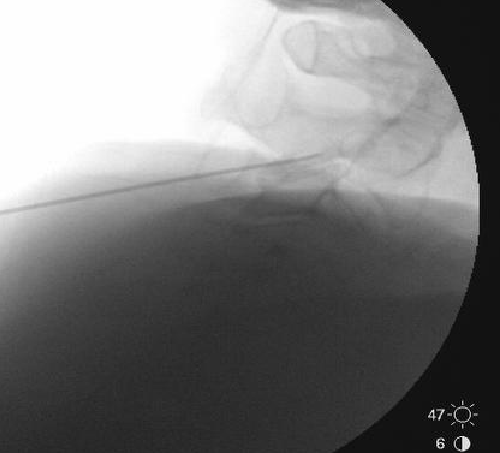

Nasty neuritis. This is 80 degrees 90 seconds.

These images look great. Sorry it happened? Steroid?

Lyrica Rx sent in, and we're starting it for chronic pain (and neuritis). She gets a shoulder scope in two weeks for a large RCT. I like antineuropathics (gabapentin 100mg HS or BID) perioperatively in general. I wish they were given 2 weeks before and after ALL orthopedic surgeries.

Dexamethasone given before RFA needles were removed.